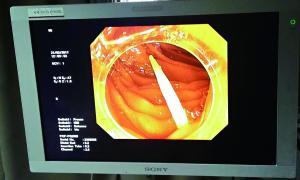

卡在肠道中的牙签的影像检查图。